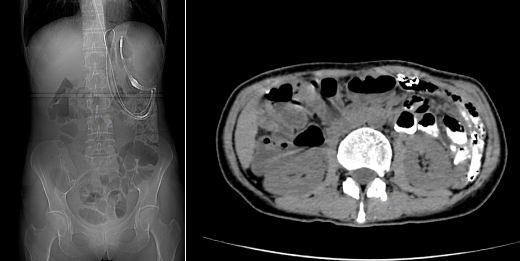

普通外一科立刻启动多学科协作(MDT)会诊,联合麻醉科、重症医学科、输血科、医学影像科等科室反复评估。考虑到患者营养状态差、直接手术风险极高,团队制定了「先改善症状、再根治肿瘤」的分步方案:第一步置入肠梗阻导管,解除小肠梗阻,让患者能正常吸收营养、恢复体力;第二步待身体条件允许后,再通过手术切除肿瘤及受侵犯脏器。

导管置入术后 3 天,患者腹痛明显缓解,能少量进食流质食物,体重也略有回升。此时结肠镜检查进一步明确:结肠脾区存在直径约 10 cm 的肿瘤,正是导致结肠梗阻的「元凶」。「时机成熟了,可以手术!」李森主任斩钉截铁地说。

手术当天,在麻醉科团队的严密监测下,李森主任带领赵本和主任、吴兵主治医师团队小心翼翼分离粘连组织,先精准定位肿瘤边界,再依次切除胰体尾、脾脏、受侵犯的部分小肠及结肠脾区肿瘤。最关键的环节是消化道重建:团队需同时完成食管空肠吻合、结肠对端吻合,确保术后消化道功能能正常运转。